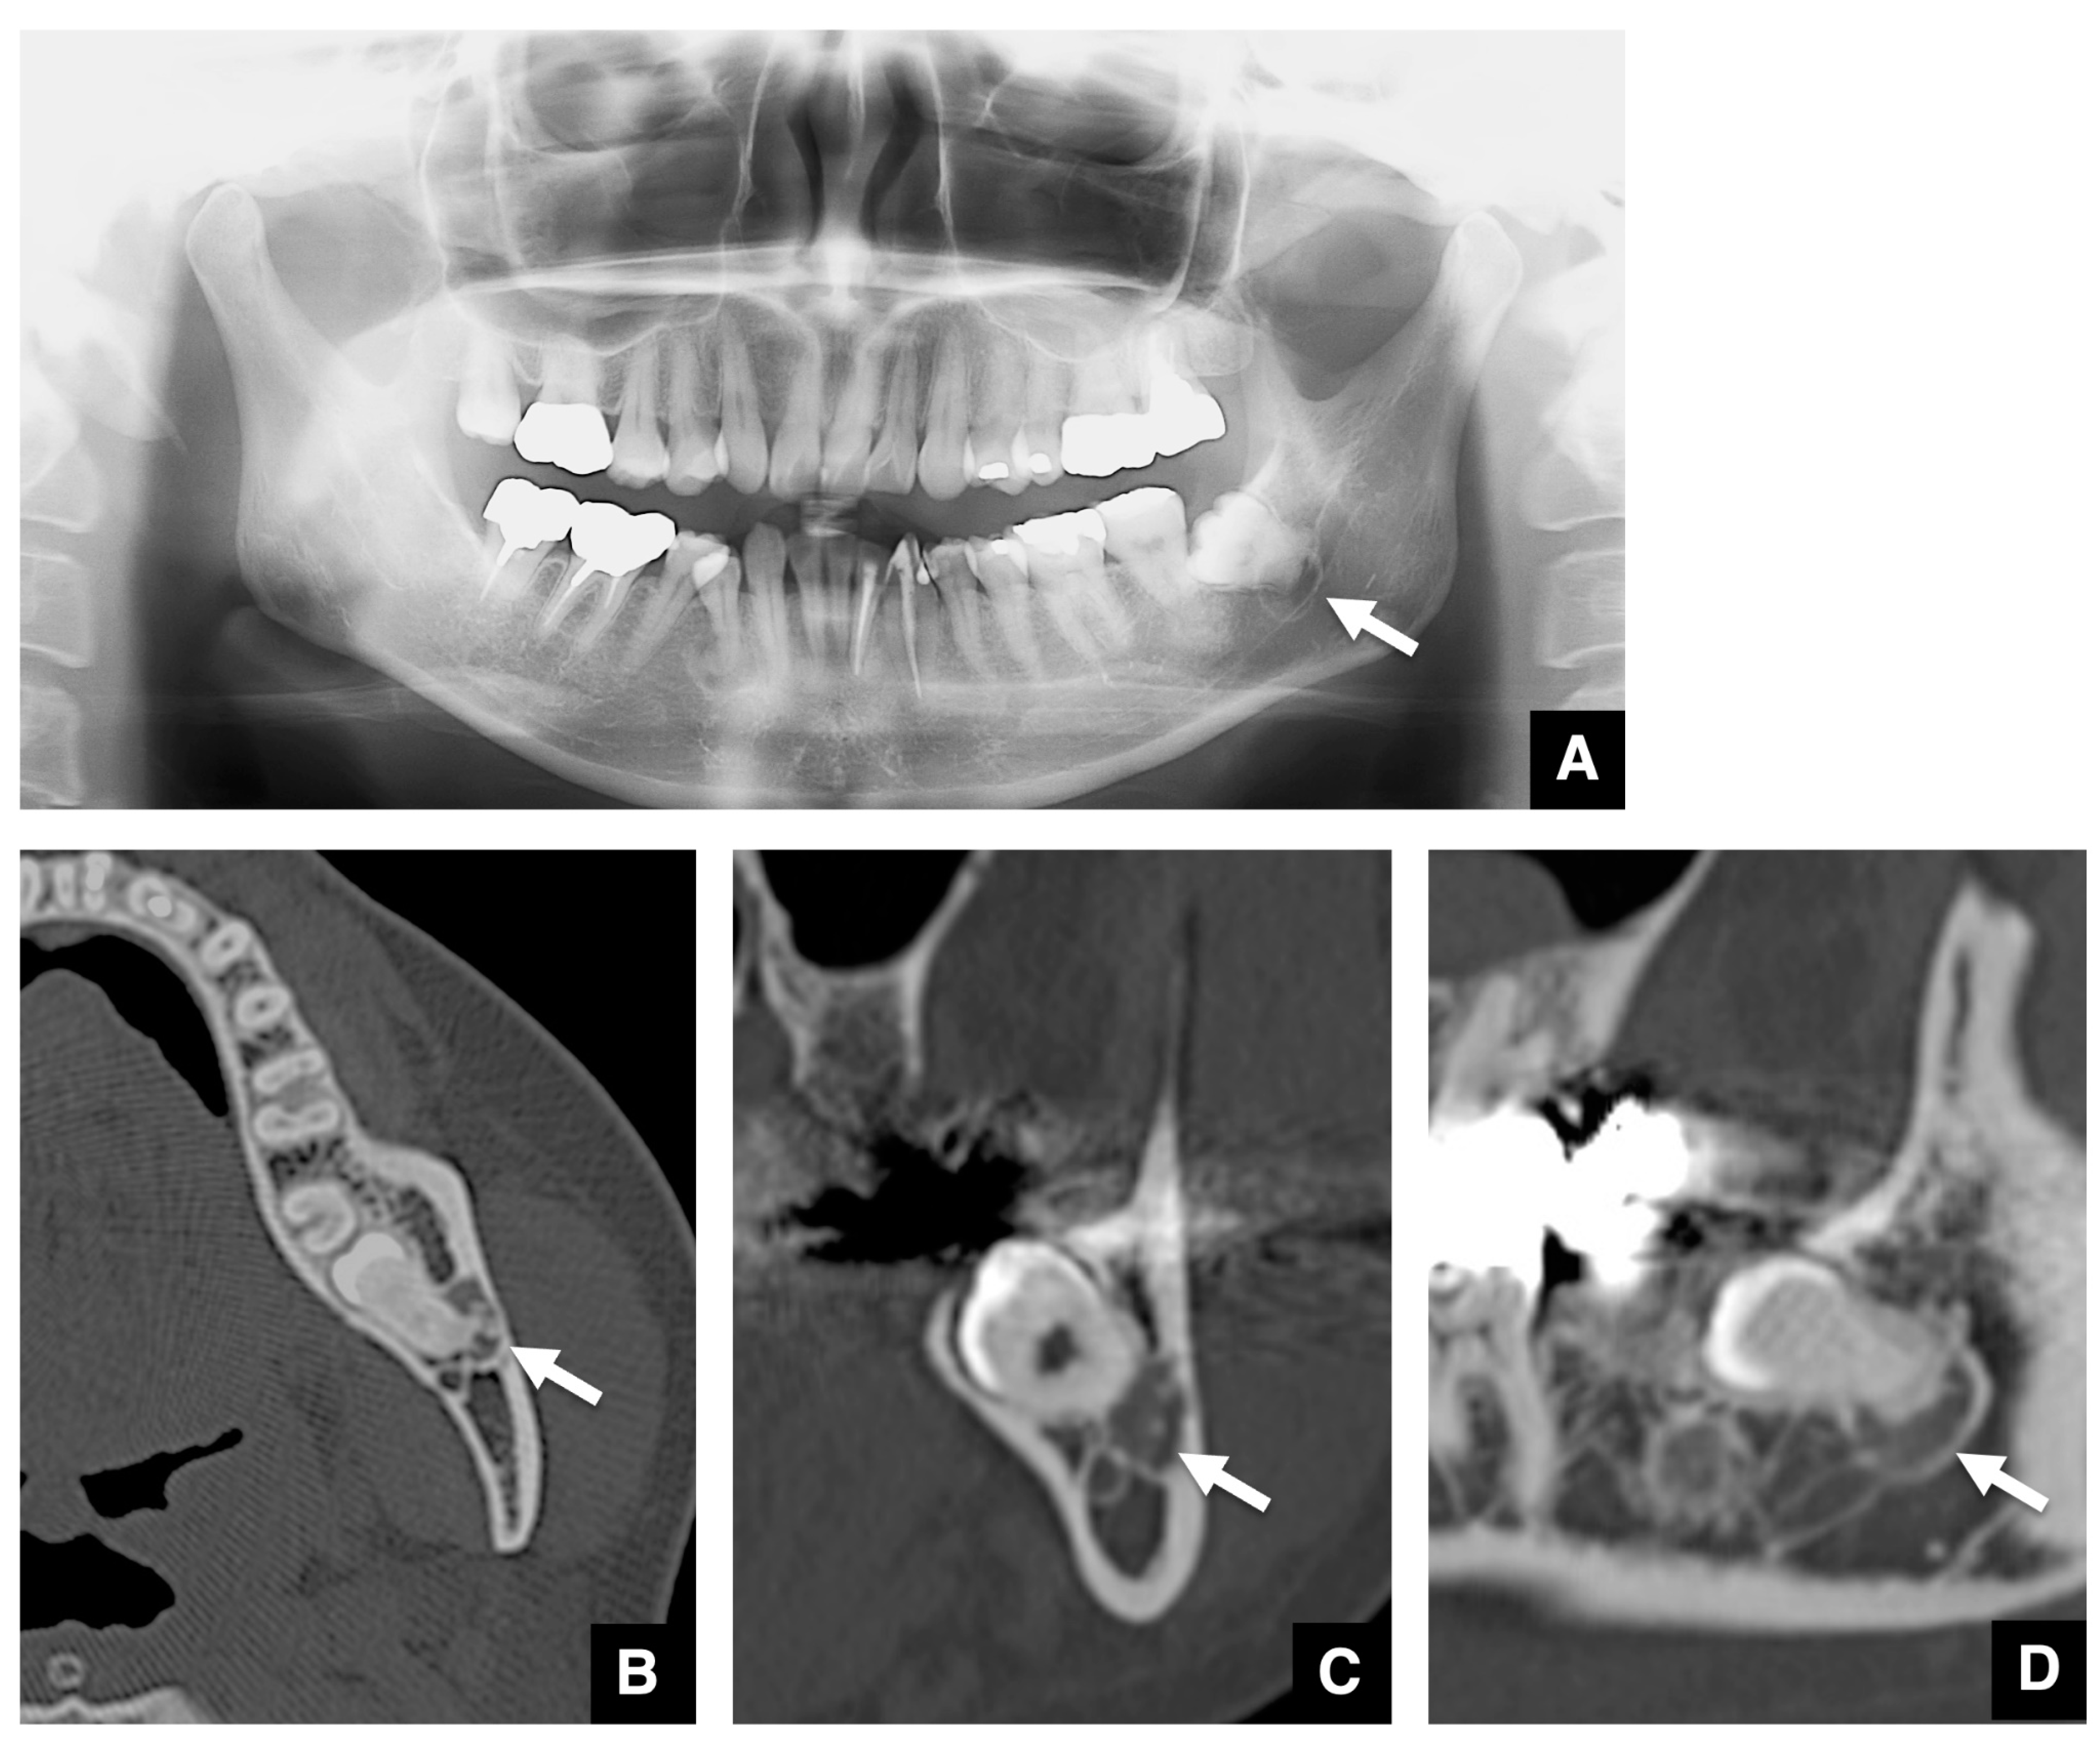

3.2. Imaging Characteristics of COD Associated with Embedded Teeth

| 48 | F | Left | Focal | Second | Round | 7.0 × 4.3 × 7.1 | Horizontal | Well-defined | Thin | Undetectable | Smooth | Present | Radiopaque dots | Distinct | Present | Present | Absent |

| 33 | F | Right | Focal | Second | Round | 8.6 × 7.0 × 7.2 | Horizontal | Well-defined | Thick | Crescent | Not smooth | Present | Uniform calcification | Distinct | Present | Absent | Absent |

| Left | Focal | Second | Round | 7.9 × 7.3 × 7.1 | Horizontal | Well-defined | Undetectable | Undetectable | Smooth | Present | Radiopaque dots | Partial contact | Present | Absent | Present | ||

| 35 | F | Right | Focal | First | Round | 9.1 × 8.6 × 10.4 | Horizontal | Ill-defined | Thin | Undetectable | Smooth | Absent | Undetectable | Distinct | Present | Absent | Present |

| 39 | F | Right | Focal | Second | Round | 14.8 × 8.5 × 9.9 | Horizontal | Well-defined | Undetectable | Crescent | Smooth | Present | Uniform calcification | Distinct | Absent | Absent | Present |

| 47 | F | Right | Focal | Second | Irregular | 8.4 × 6.0 × 9.7 | Vertical | Well-defined | Undetectable | Pearls | Not smooth | Absent | Massive calcification | Partial contact | Present | Absent | Present |

| 42 | F | Left | Focal | Second | Irregular | 10.2 × 5.6 × 13.0 | Horizontal | Well-defined | Undetectable | Multiple dots | Smooth | Present | Radiopaque dots | Distinct | Present | Absent | Present |

| 51 | F | Right | Focal | Second | Round | 9.8 × 6.2 × 5.8 | Horizontal | Ill-defined | Undetectable | Crescent | Smooth | Present | Uniform calcification | Partial contact | Absent | Absent | Present |

| 33 | F | Left | Focal | Second | Round | 10.3 × 8.7 × 11.5 | Vertical | Ill-defined | Undetectable | Multiple dots | Smooth | Present | Massive calcification | Contiguous | Present | Absent | Present |

| 62 | M | Right | Focal | First | Round | 6.0 × 2.9 × 5.7 | Horizontal | Well-defined | Undetectable | Undetectable | Smooth | Present | Undetectable | Distinct | Absent | Absent | Absent |

| 44 | M | Left | Focal | First | Round | 8.7 × 5.7 × 5.8 | Horizontal | Ill-defined | Undetectable | Undetectable | Smooth | Absent | Undetectable | Distinct | Absent | Absent | Absent |

| 45 | F | Right | Florid | Second | Round | 11.9 × 8.6 × 11.7 | Horizontal | Ill-defined | Undetectable | Undetectable | Smooth | Present | Multiple radiopaque dots | Partially contact | Absent | Absent | Present |

| Left | Florid | Second | Round | 10.2 × 5.6 × 11.9 | Horizontal | Ill-defined | Thin | Multiple dots | Not smooth | Present | Multiple radiopaque dots | Partially contact | Present | Absent | Present | ||

| 38 | F | Left | Focal | Final | Round | 13.2 × 9.8 × 10.2 | Horizontal | Well-defined | Thick | Pearls | Not smooth | Absent | Uniform calcification | Contiguous | Present | Absent | Absent |

| 35 | F | Left | Focal | Second | Round | 11.7 × 7.1 × 10.0 | Horizontal | Well-defined | Thin | Multiple dots | Smooth | Present | Radiopaque dots | Partial contact | Present | Absent | Present |